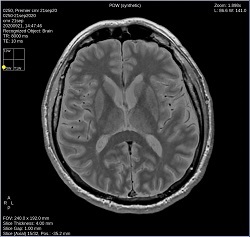

Click PDW to change the image contrast to PD-weighted synthetic.

Click T1W FLAIR to change the image contrast to synthetic T1 FLAIR-weighted.